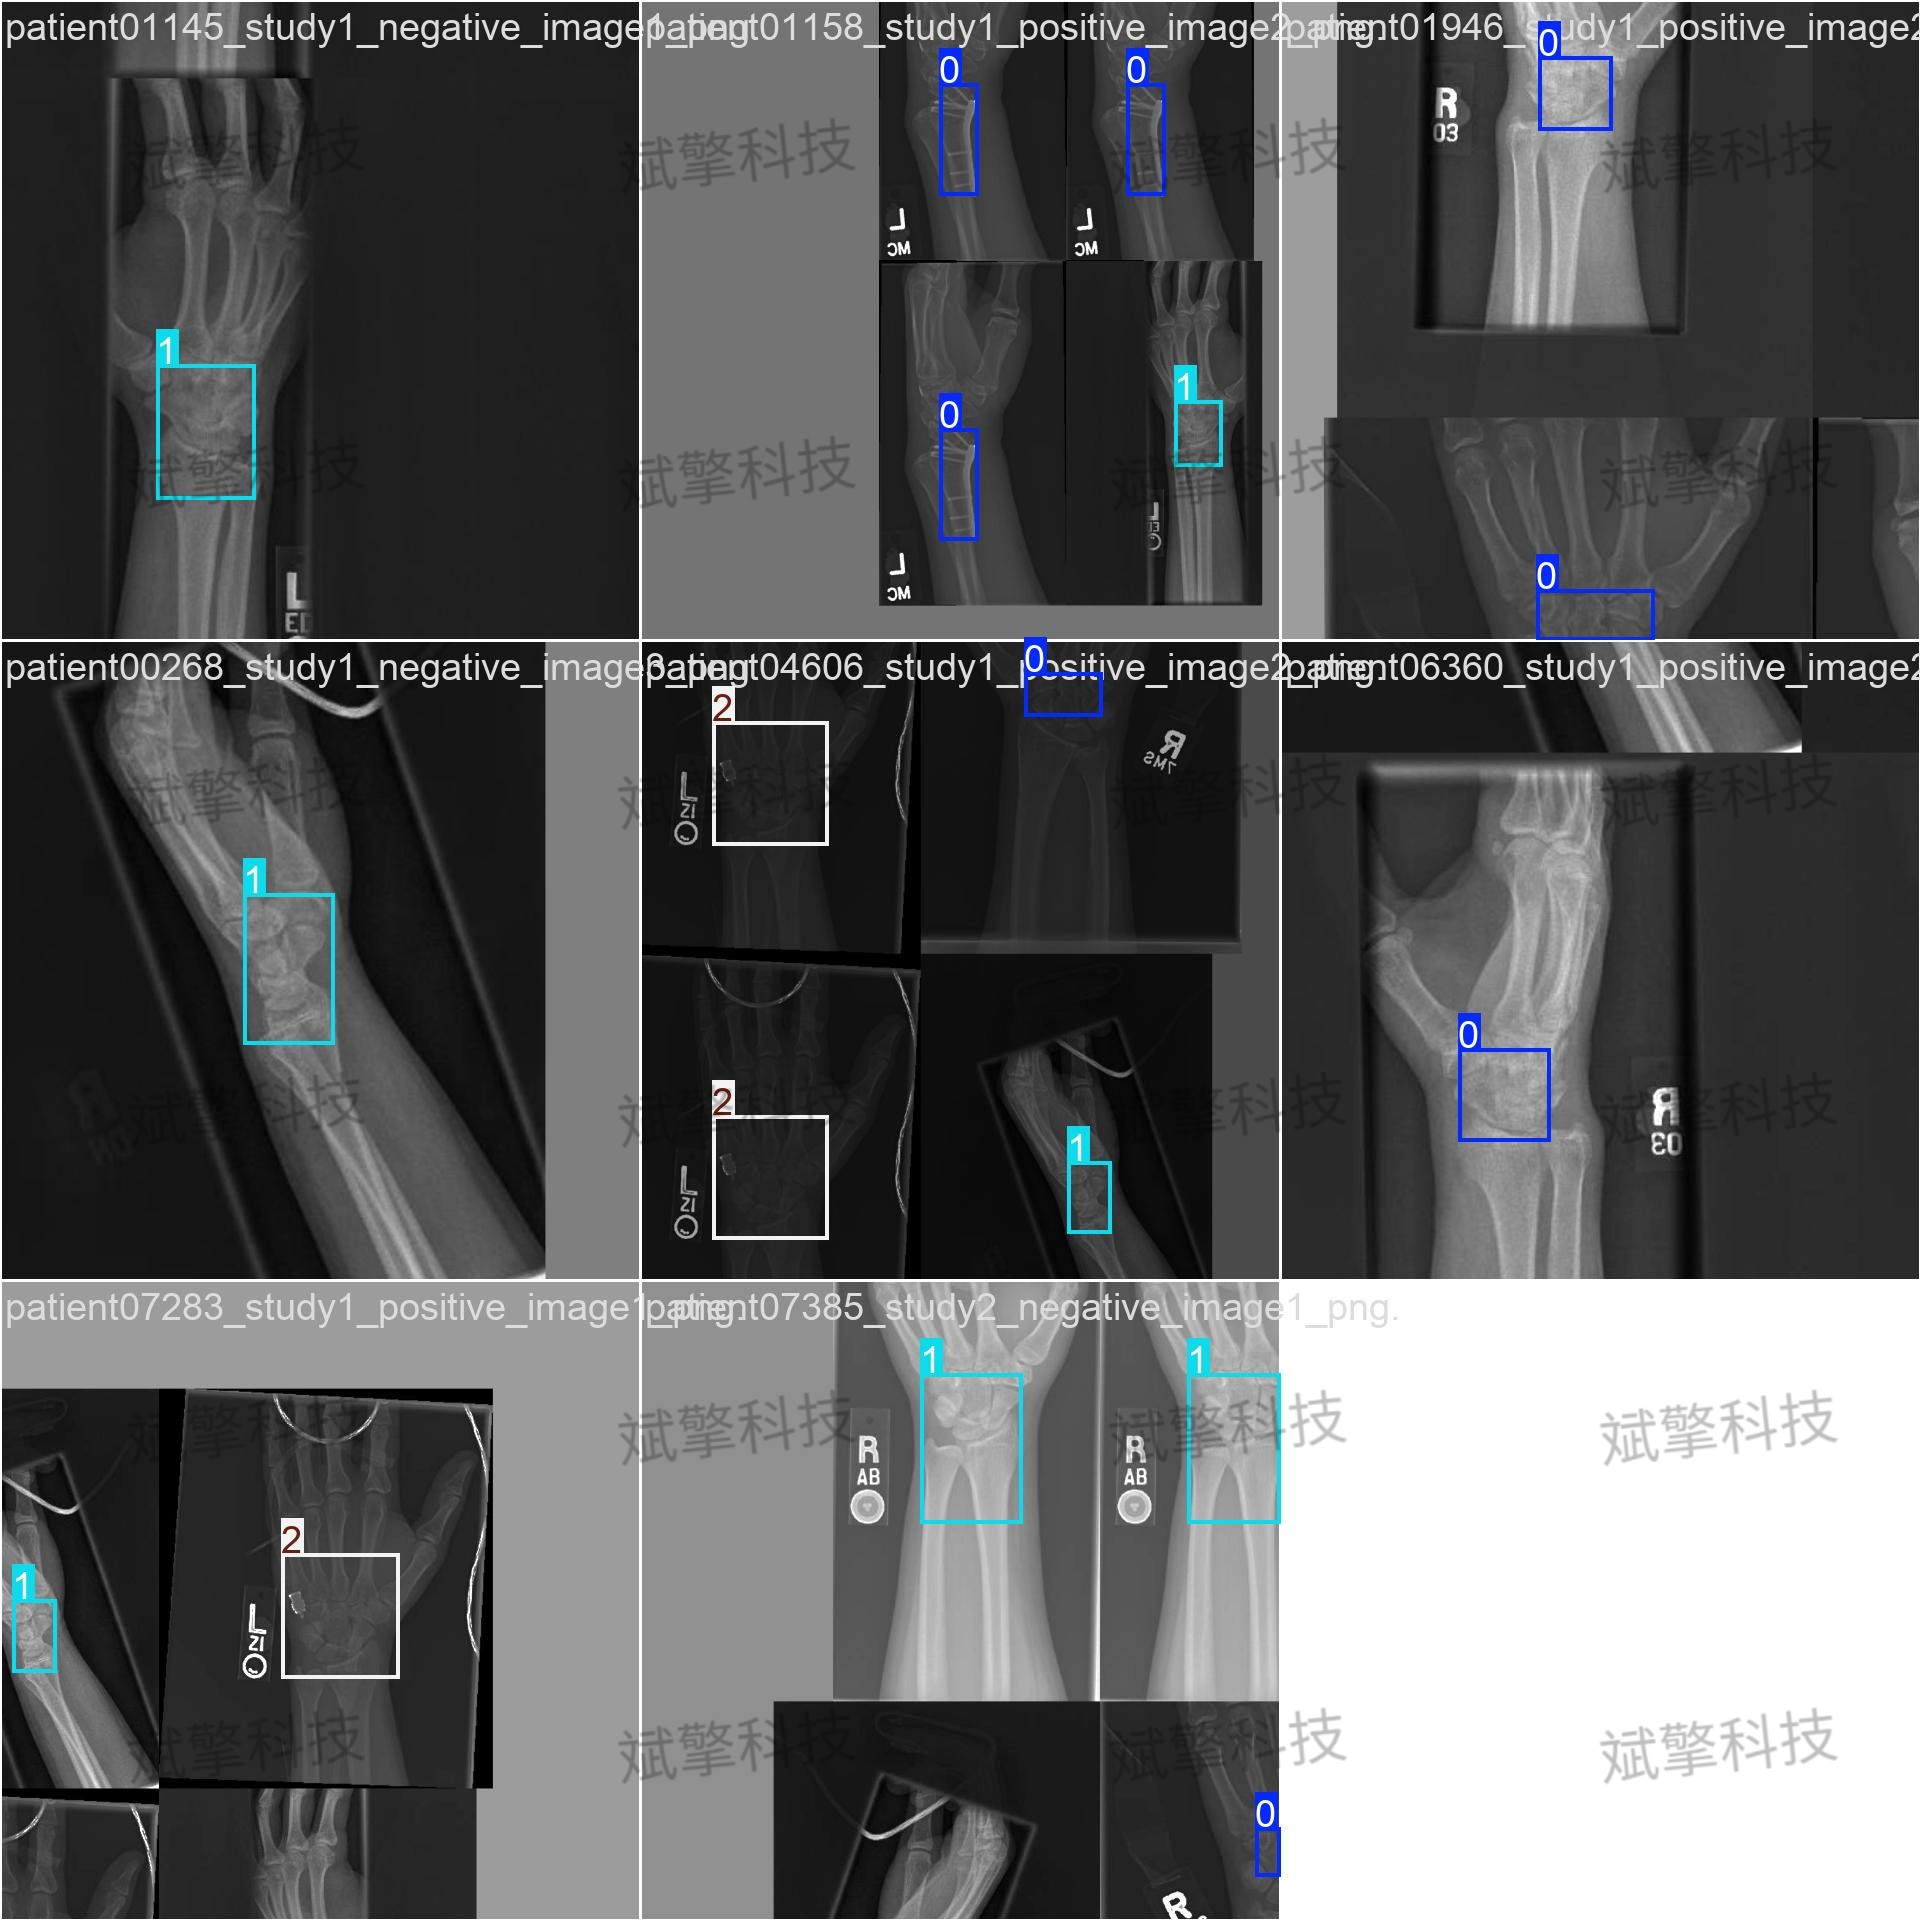

本研究提出了一种基于YOLO26目标检测框架的骨折识别系统,旨在通过深度学习技术实现对医学影像中骨折区域的自动定位与分类。该系统构建了一个包含“Fracture”(骨折)、“No_Fracture”(无骨折)和“object”(物体)三类目标的数据集,涵盖训练集2108张、验证集602张及测试集301张图像。实验结果显示,模型在验证集上的平均精度(mAP50)达到了0.501。本研究为医学影像辅助诊断提供了初步的技术验证,未来工作将聚焦于数据增强、类别定义优化及模型轻量化,以提升骨折识别的准确性和临床实用性。

数据集介绍

本研究所使用的数据集是专为骨折检测任务构建的,包含训练集、验证集和测试集三个部分,具体分布如下:

数据集划分:

- 训练集:2108 张图像,用于模型参数的学习和优化。

- 验证集:602 张图像,用于在训练过程中监控模型性能、调整超参数及防止过拟合。

- 测试集:301 张图像,用于最终评估模型的泛化能力。

-

类别定义:

数据集包含3个目标类别,其定义如下:- Fracture:标记图像中存在骨折的区域。

- No_Fracture:标记图像中无骨折的骨骼区域(或正常骨骼)。

- object:标记图像中的其他物体(如医疗器械、背景干扰物等)。